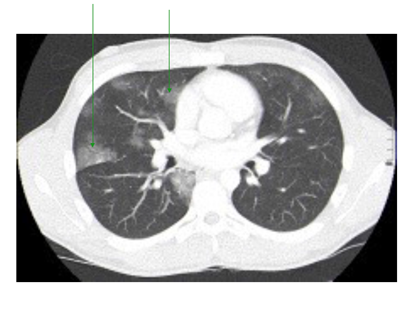

He was kept on supplementary oxygen, started on intravenous morphine for analgesia, intravenous normal saline and kept fasted. An initial portable chest x-ray was normal as shown in Figure 1.

Figure 1 Normal chest x-ray. No evidence of the tracheal injury on the x-ray.